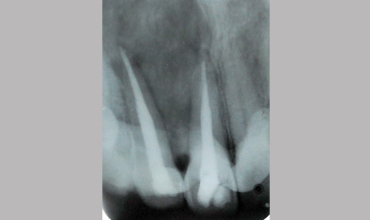

Surgical Management Of Large Periapical Cyst